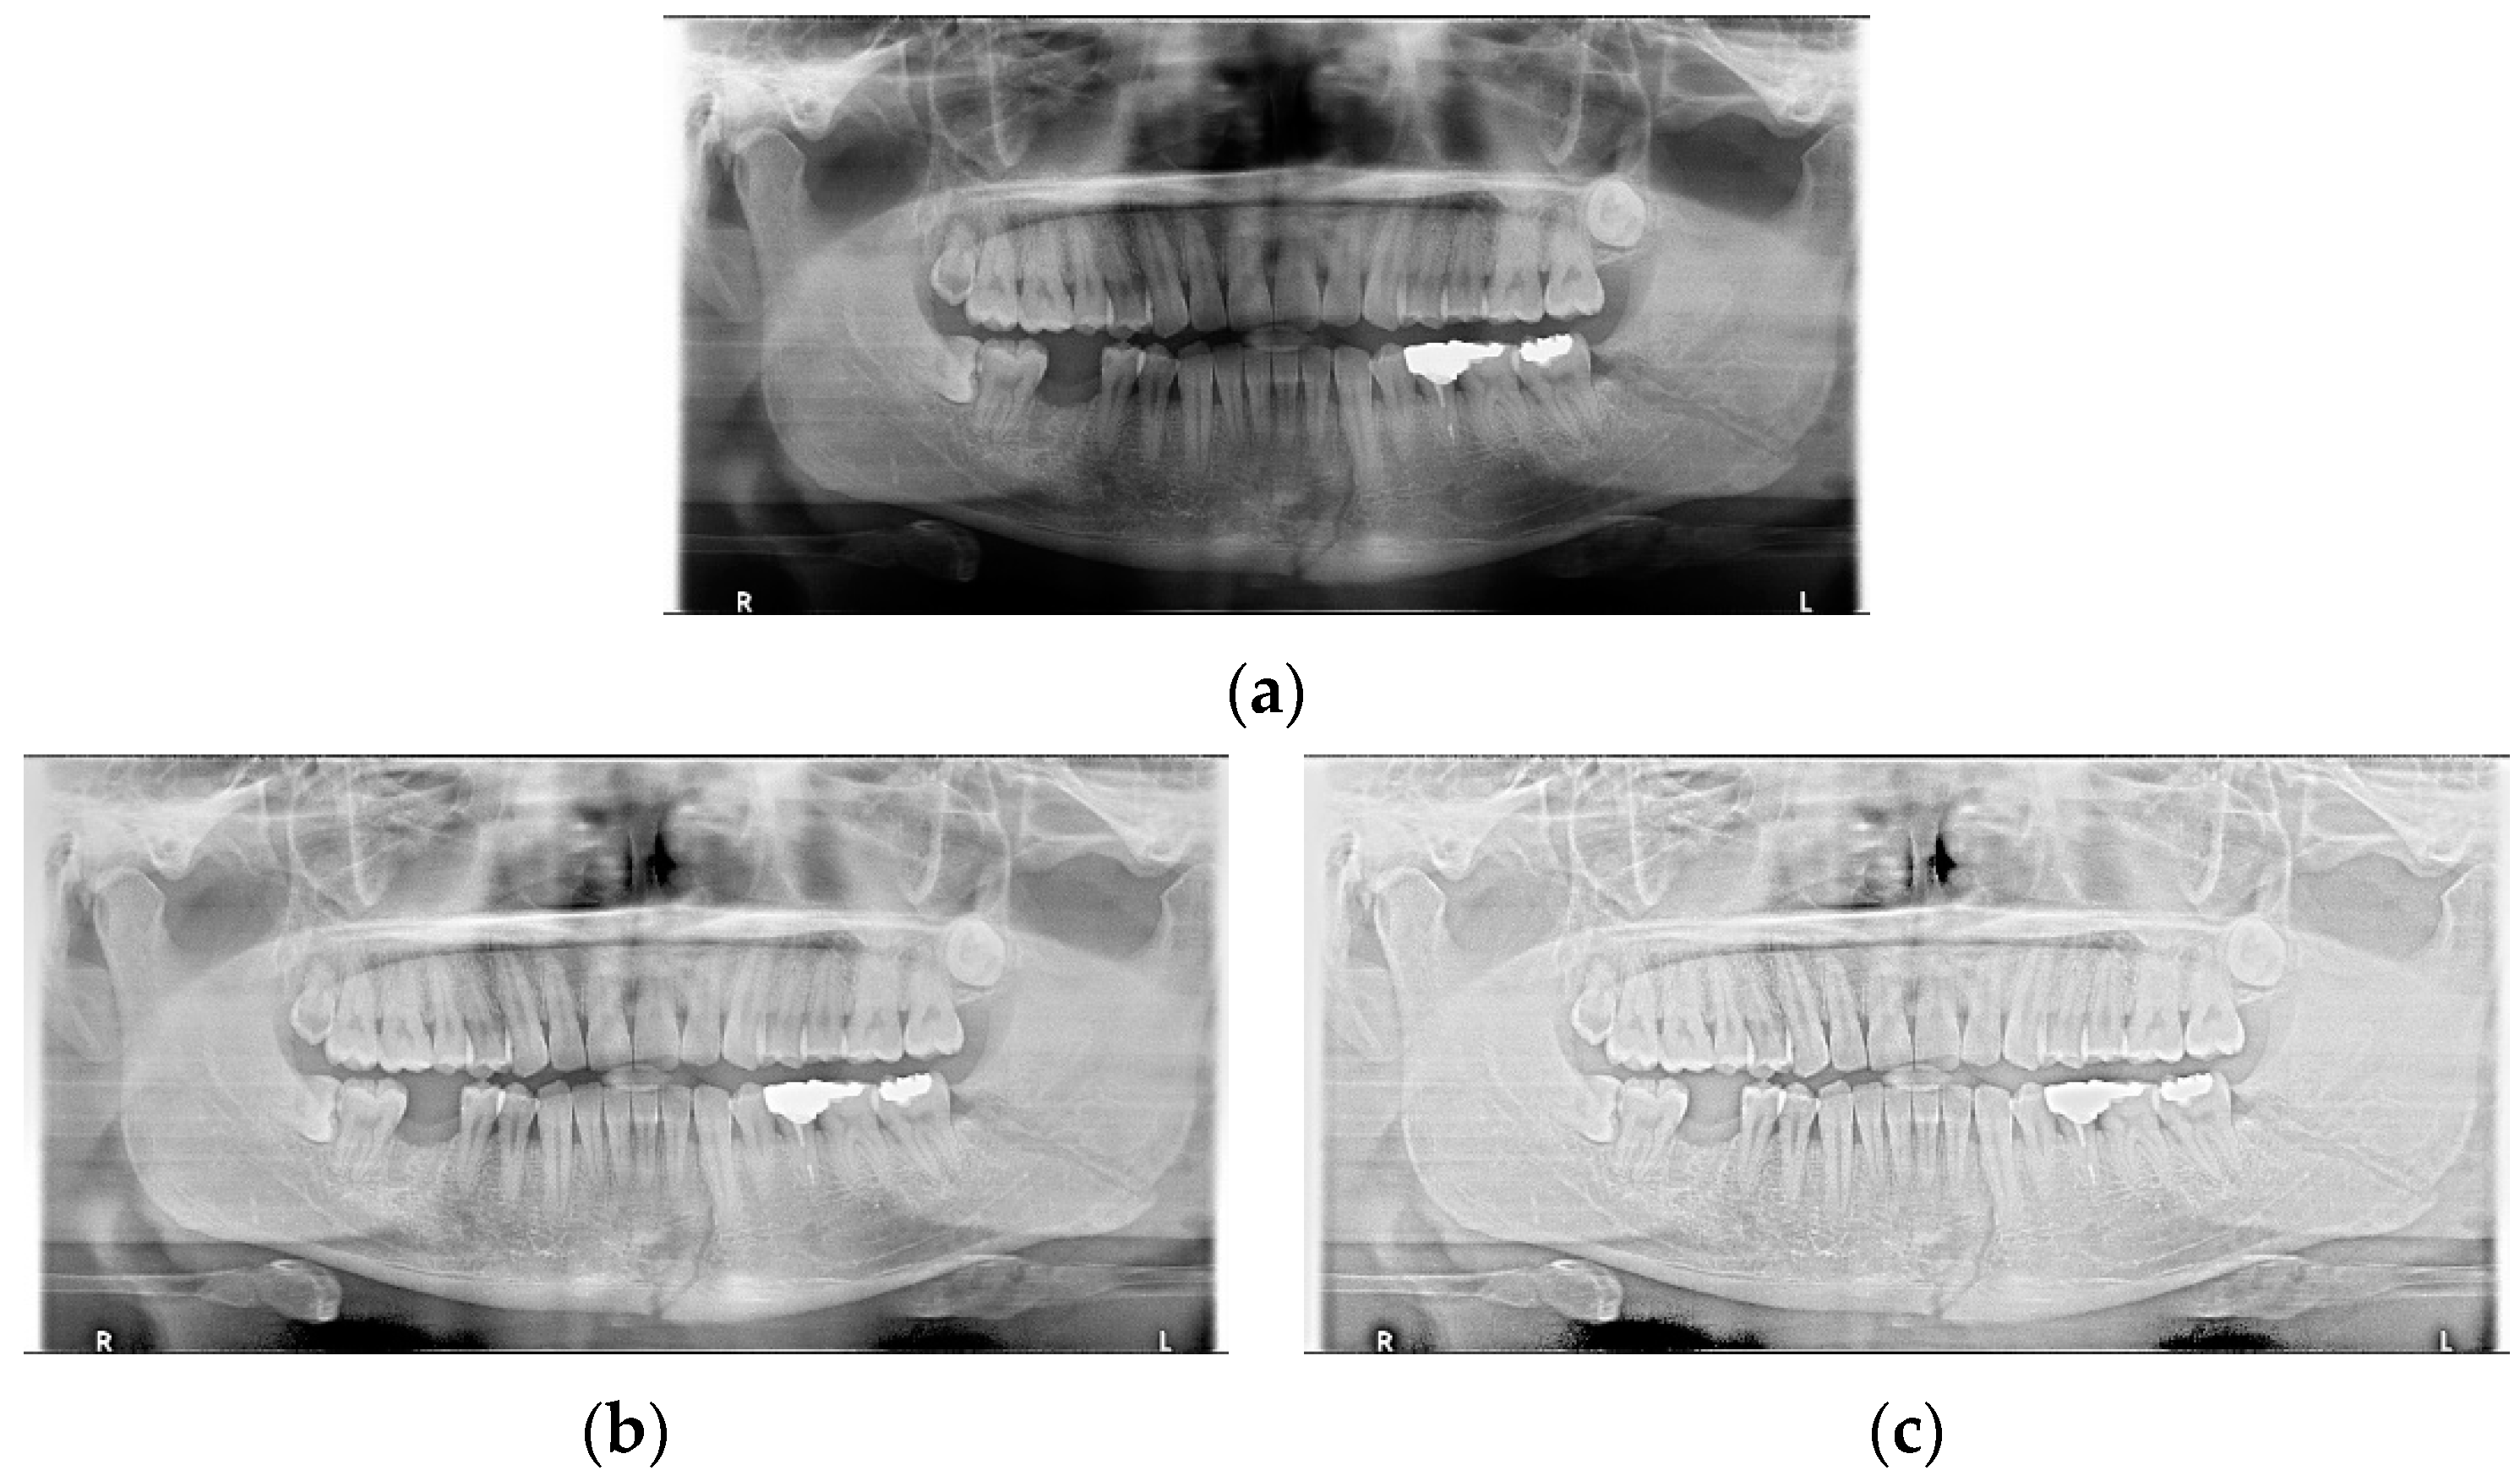

Data augmentation significantly improved the accuracy of the module during training. In the case of the LAT YOLOv4 module, the detection performance was improved by increasing the number of training data images using LAT and gamma correction, which are image pre-processing and data augmentation provided by default. LAT processes images in two ways: single-stage luminance adaptation transform (SLAT) and multiple-stage luminance adaptation transform (MLAT) [17]. As shown in Figure 5, SLAT strongly enhances the local details of the panoramic image; therefore, the image becomes brighter overall. Compared with SLAT, MLAT improves the visual performance of an image through tone compression of the entire image rather than local details. The LAT-processed panoramic image emphasizes the mandibular fracture better than the conventional image.

Figure 5.

The panoramic radiographs: (a) normal panoramic radiograph, (b) multiple-stage luminance adaptation transform (MLAT) panoramic radiograph, and (c) single-stage luminance adaptation transform (SLAT) panoramic radiograph.